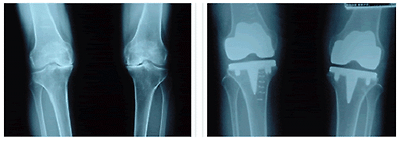

◆ Total Knee Replacement

-인공 슬관절 전치환술은 무릎 관절을 형성하는 손상된 골을 제거하고 특수 합금과 고분자 물질로 구성된 인공 관절을 고정함으로써 변형이 교정되어 무릎 관절의 통증이 없는 동작이 가능해 지면서 보행을 포함한 일상적인 생활이 가능하게 해주는 수술

-위쪽 허벅지 뼈에는 정상적인 사람의 뼈와 거의 흡사한 모양을 가진 금속구성물(대퇴골 구성물)로을 이용해서 표면을 대신함

-아래쪽 정강이뼈에는 평평한 모양을 한 금속 구성물(경골 구성물)로 대체하게 되고, 연골기능을 대신하도록 만들어진 플라스틱판을 끼워 넣어서 관절이 부드럽게 움직일 수 있도록 함